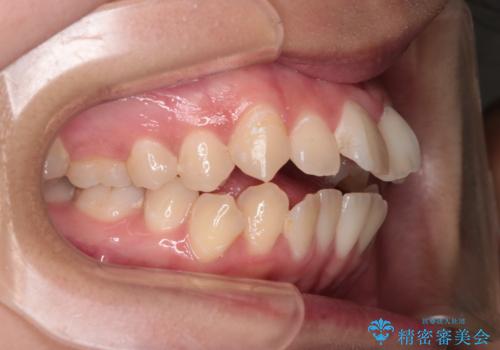

【インビザライン】シザーズバイト、抜歯矯正

- オープンバイトを主訴に来院された患者様です。

抜歯を行うことで、インビザラインを用いて前歯を下げることができ、同時にオープンバイトを改善することができました。

今回はインビザラインのみで治療を終了することができました。